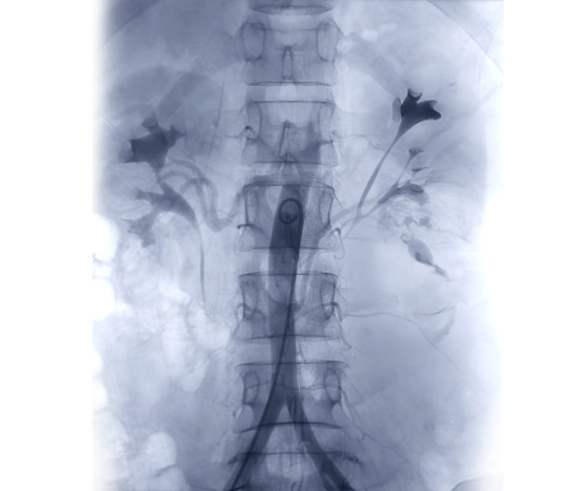

Хірург транскутанно виконує пункцію радіальної, плечової чи загально-стегнової артерії або вени, селективно вводить контрастну речовину в цільове артеріальне або венозне русло для фіксації судинної патології, далі за допомогою направляючого катетеру вводить внутрішньо-судинні провідники діаметром (0,035’’, 0,018’’, 0,014’’) до цільового судинного басейну та за системою «monorail» доставляє катетер для емболізації. Виконує не селективну чи селективну емболізацію судинного русла: емболізаційними спіралями чи мікрочастинками. Кінцевий результат фіксує контрастним заповненням судинного басейну на ангіографі у різних проекціях. Після виконання дослідження хірургічний інструментарій видаляється та виконується гемостаз судинного доступу.